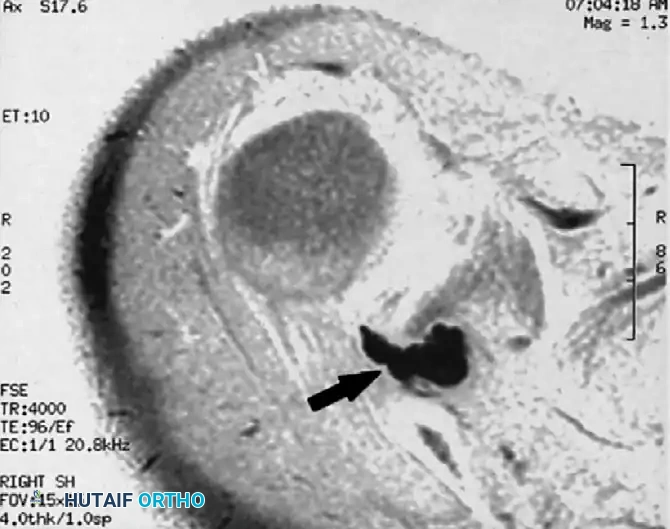

The following MR images demonstrate the classic presentation of a paralabral ganglion cyst causing entrapment neuropathy of the suprascapular nerve at the spinoglenoid notch:

FIGURE 46-16A: Axial MR image. Arrowheads indicate a small, low-density shadow situated just posterior to the neck of the glenoid, representing the early formation of a paralabral cyst.